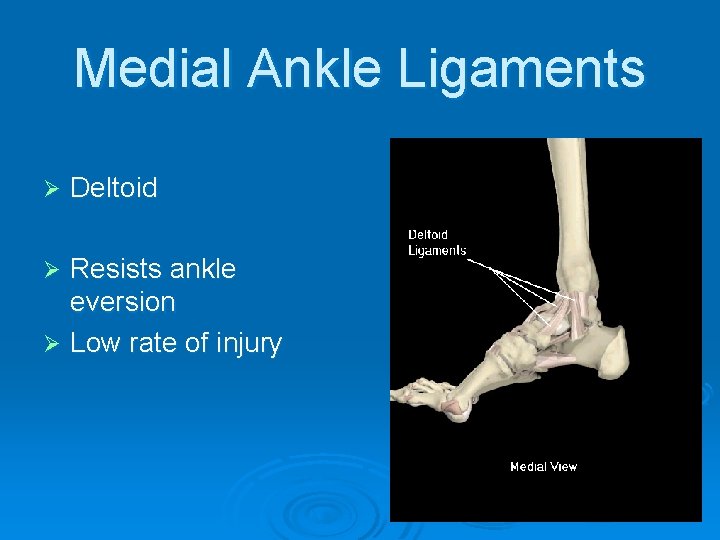

Medial Ankle Ligaments Ø Deltoid Resists ankle eversion Ø Low rate of injury Ø